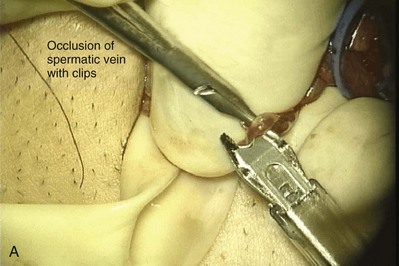

Inguinal hernia repair, particularly when performed in childhood, is known to be associated with vasal injury leading to obstruction. If there is no previous inguinal incision and the side of obstruction is unknown, the testis is delivered through a high vertical scrotal incision (see Scrotal later). The vas deferens is identified and isolated at the junction of the straight and convoluted portions of the vas deferens. Using an operating microscope and 10-power magnification, the vasal sheath is longitudinally incised and the vasal vessels carefully preserved (Fig. 22–3A).

Figure 22–3 A, Using an operating microscope and 10× magnification, the vasal sheath is longitudinally incised and vasal vessels carefully preserved. B, Under 25× magnification, a 15-degree microknife is used to hemitransect the vas until the lumen is revealed.